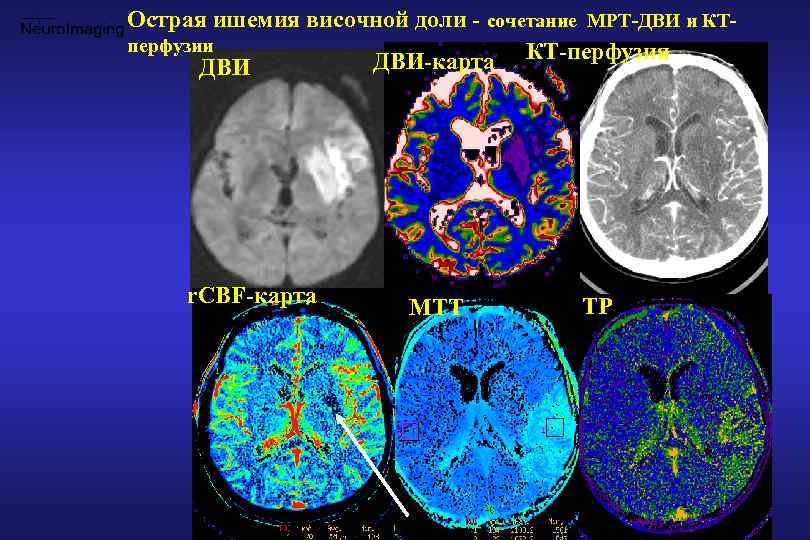

Внутричерепная гипотензия: КТ-исследования и их интерпретация